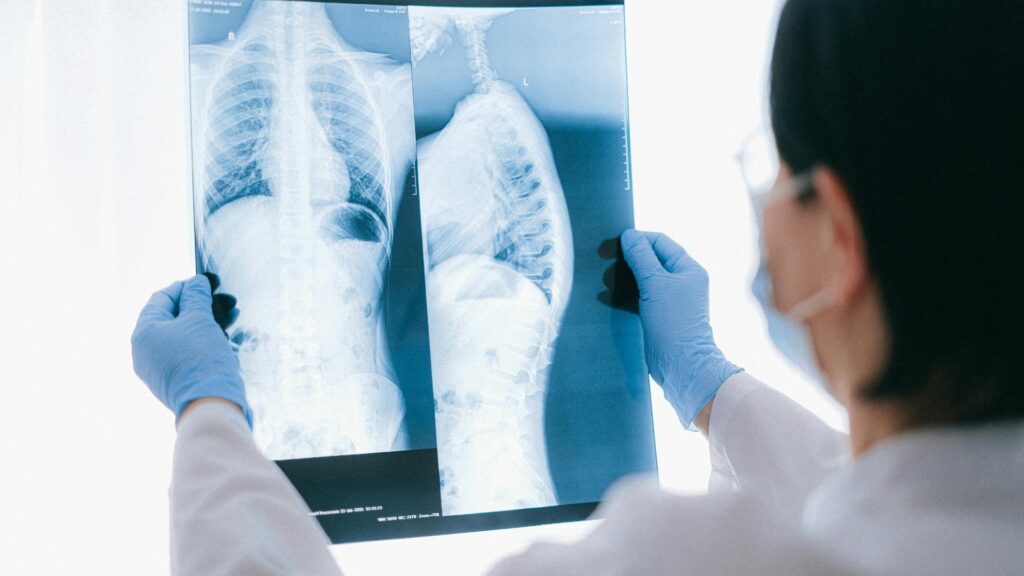

O mediastino é frequentemente descrito como uma “caixa de surpresas”, mas, felizmente para o cirurgião, as patologias que o habitam respeitam barreiras anatômicas rigorosas. A avaliação inicial de qualquer massa mediastinal baseia-se em três pilares fundamentais: Idade, Sexo e Localização. Desses, a localização é o fator preditivo mais forte, definindo o diagnóstico provável em cerca de 80% dos casos.

A divisão anatômica é o mapa que orienta a suspeita diagnóstica e a conduta:

• Mediastino Anterior (60% das massas): É a região mais nobre e frequentemente acometida. As principais etiologias formam o clássico grupo dos “Ts” e linfomas: Timoma (30%), Linfoma (25%) e Tumores de Células Germinativas (15% – Teratomas).

• Mediastino Médio (20%): Predomínio de lesões císticas (Cistos Broncogênicos, Pericárdicos, Esofágicos) e Linfonodomegalias (Linfomas ou Metástases).

• Mediastino Posterior (20%): O reino dos Tumores Neurogênicos (como os Schwannomas).